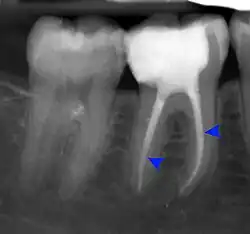

Decay (green) with apical abscess (blue) -